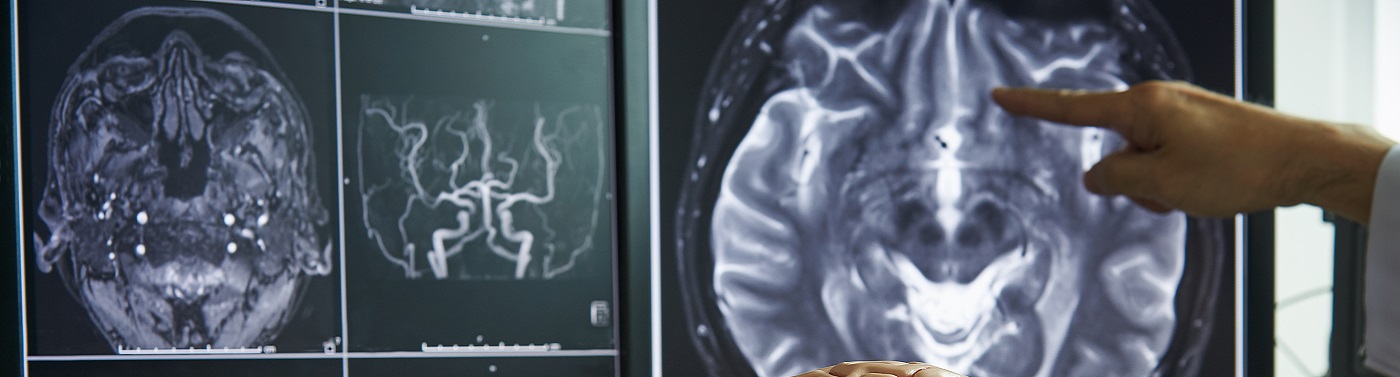

Infraestructura de quirófanos – quirófano endovascular y equipamiento (resonancia magnética y tomografía de alta resolución, angiógrafo General Electric Allura flat panel, microscopio quirúrgico Carl Zeiss Pentero), permiten óptimo diagnóstico y tratamiento de casos complejos.